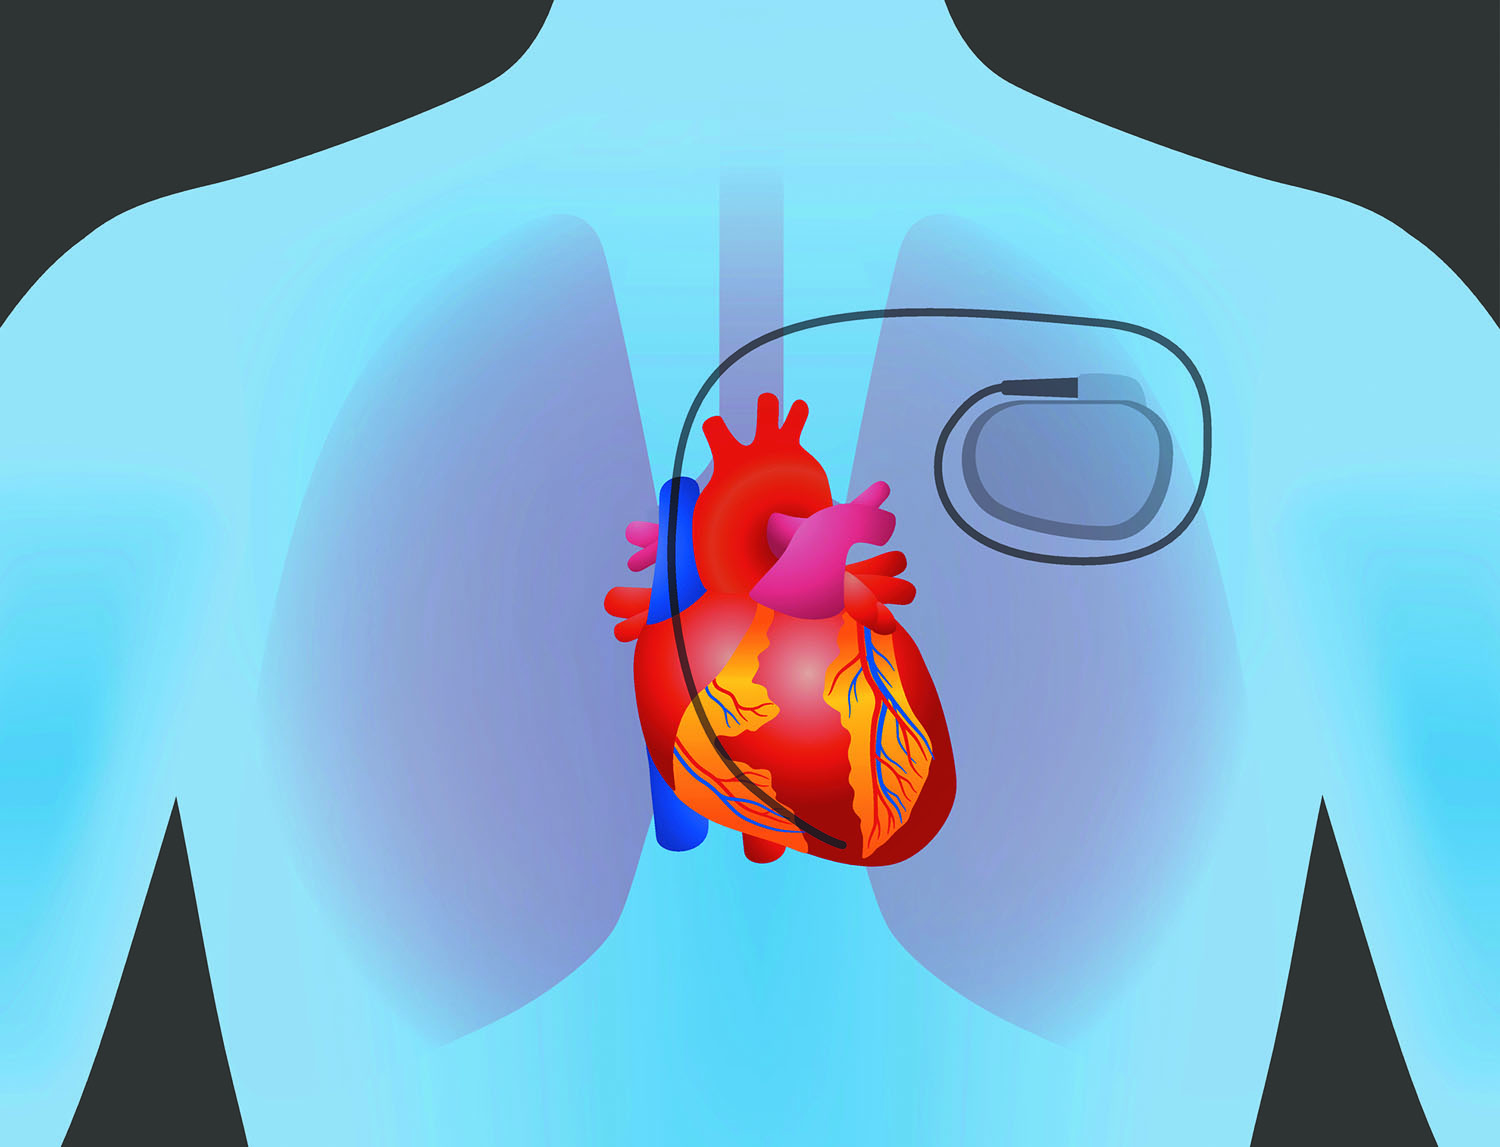

ឧបករណ៍រំញោច ឬជំនួយបេះដូង Pacemaker